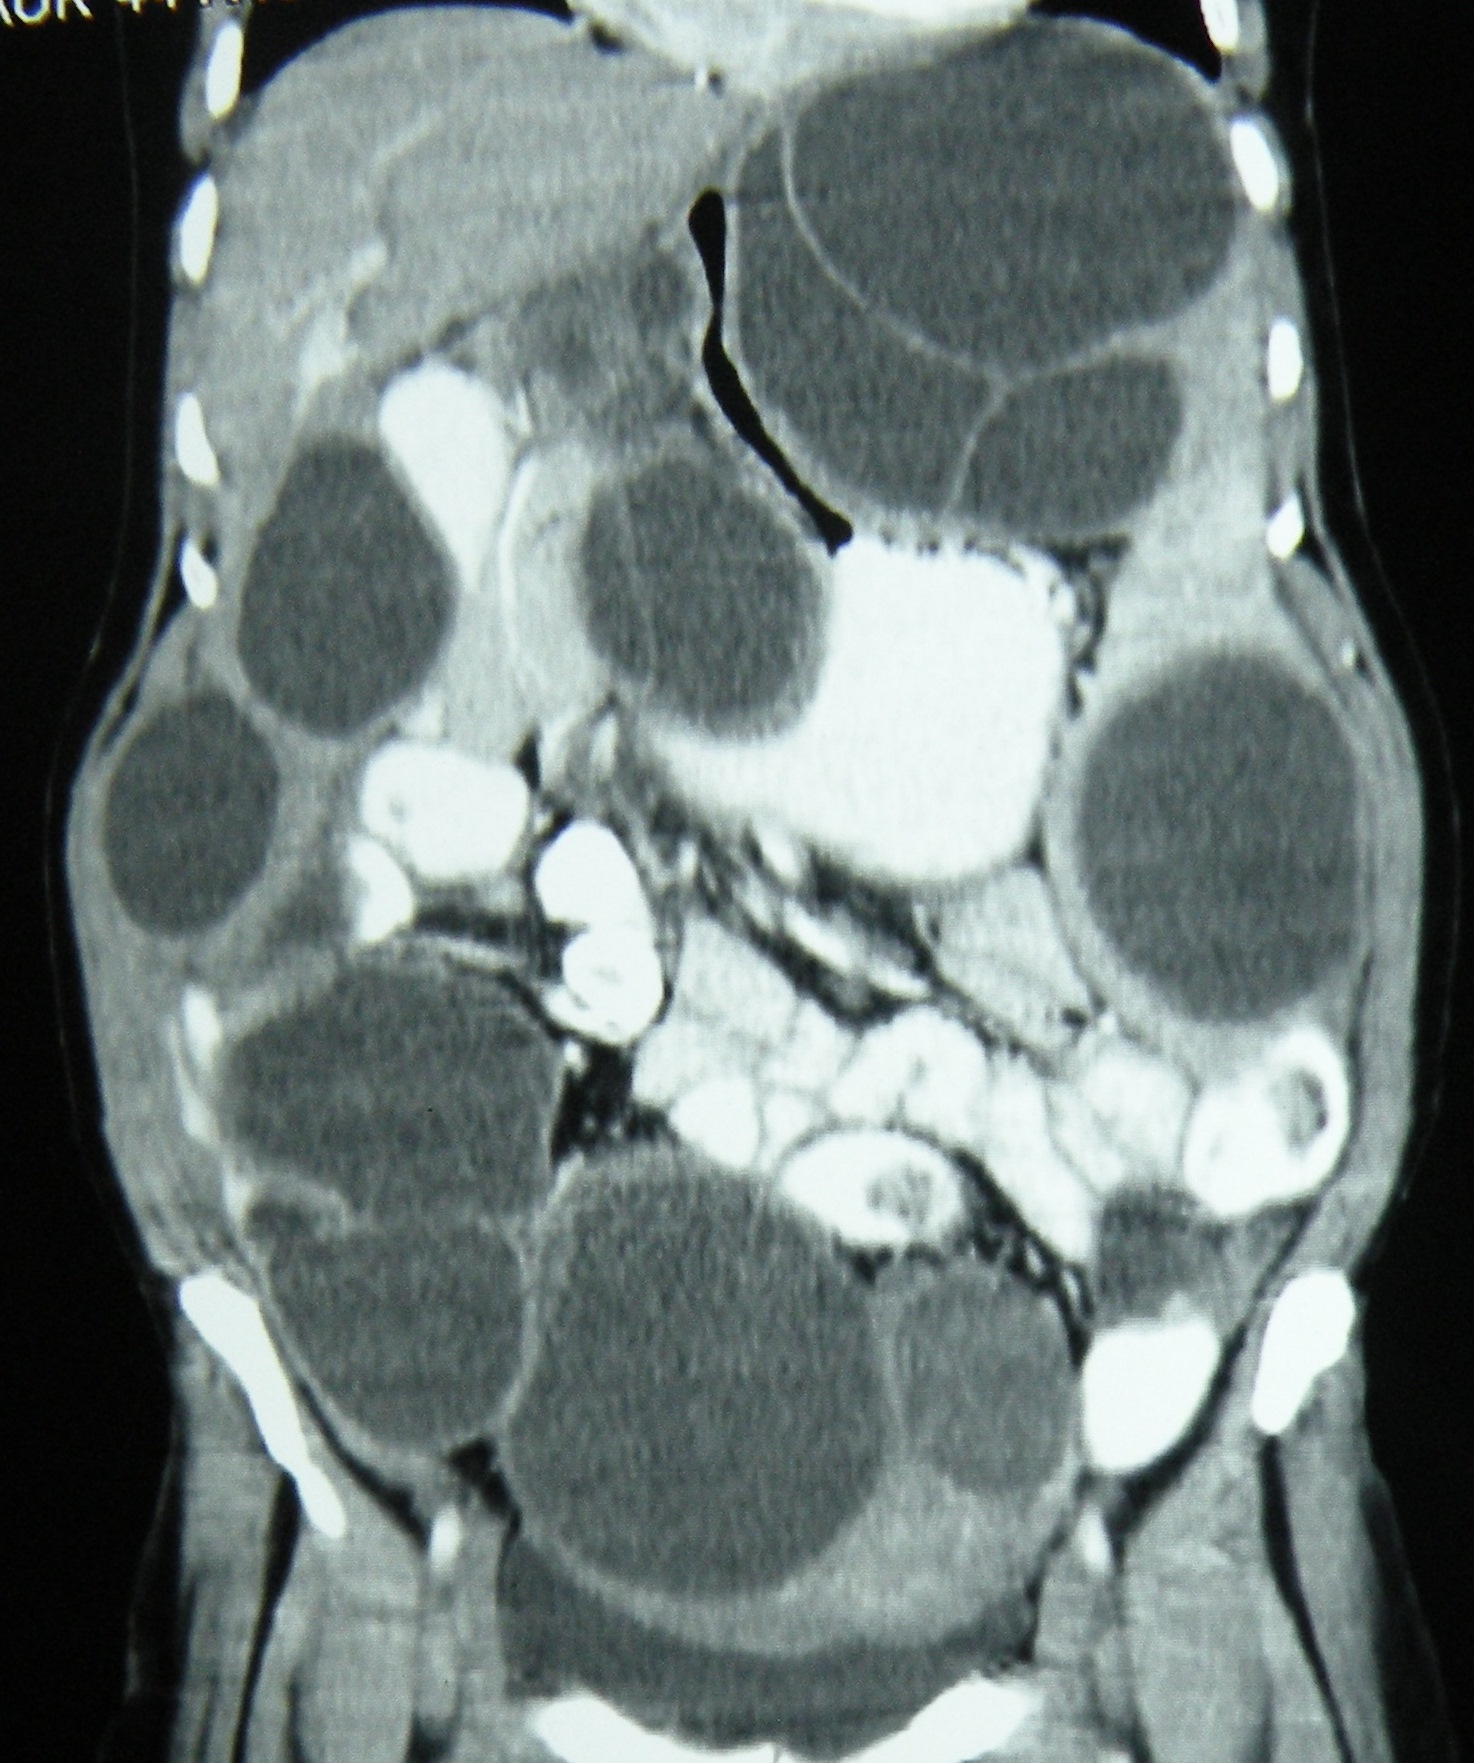

Intraperitoneal and retroperitoneal hydatids in a 55 years old woman, all excised over a period of more than 2 and 1/2 hours.